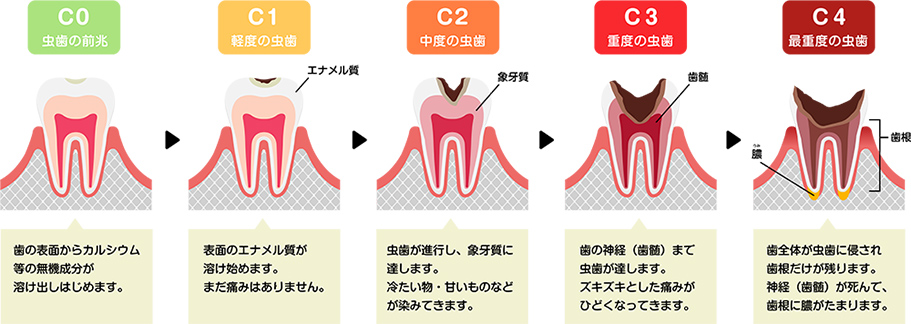

むし歯は「C0」「C1」「C2」「C3」「C4」という段階で分けられています。進行の度合いに応じた治療で、噛む機能を「詰め物」や「かぶせ物」をして補います。

むし歯部分を削り取り、穴の部分に保険適用の白いコンポジットレジンと呼ばれる合成樹脂を詰めていきます。 型取りが必要なく、その日のうちに治療が終わります。

エナメル質の奥にある象牙質に達した場合、むし歯部分を取り除いた後に型を採り、修復物(詰め物やかぶせ物)を作製し装着します。

むし歯菌に感染した神経を除去し、内部を洗浄・消毒して薬剤を詰めることで歯を残す「根管治療」を行います。

歯を残すことが難しい状態のため抜歯を行い、入れ歯などの治療を行って噛む機能を回復させます。

根だけになった歯は放置しておくと、根の先に潜んでいるむし歯菌によって痛みが起こり、「骨髄炎」を引き起こしてしまいますので早急に治療しましょう。